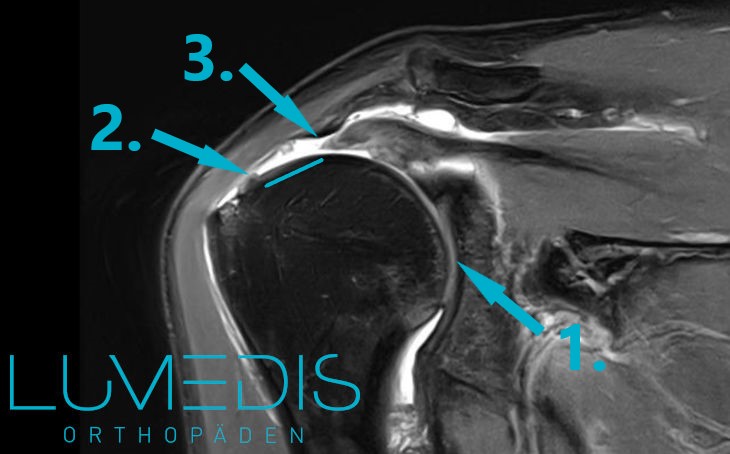

Diese diagnostische Methode kommt vor allem bei unklaren Befunden zum Einsatz. Auch der Ausschluss möglicher Begleitverletzung oder die Abgrenzung zu anderen Verletzungsarten kann im MRT gut erfolgen.

Bei einer unklaren Einteilung der Ausprägung der Verletzung der Supraspinatussehne ist ein MRT der Schulter ebenfalls sinnvoll, da hier beim Vorliegen einer Ruptur die Position der beiden gerissenen Enden bestimmt werden kann.

MRT einer Supraspinatussehnenruptur rechts (T2)